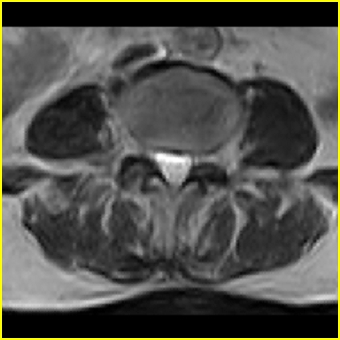

右侧黄韧带肥厚或钙化,压迫马尾神经所致。必要时行ct扫描。

我认为这一层面椎间盘应该合并左外侧型突出。

黄韧带肥厚.